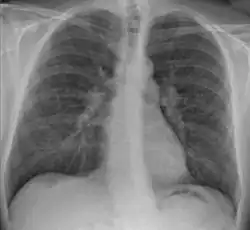

Chest X-ray showing the typical nodularity of sarcoidosis, predominantly in the hila of the lungs. | |